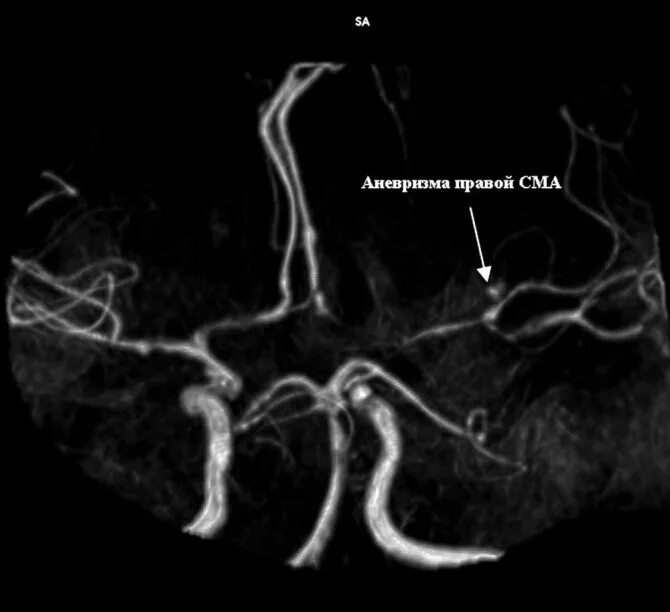

Мешотчатая аневризма внутренней